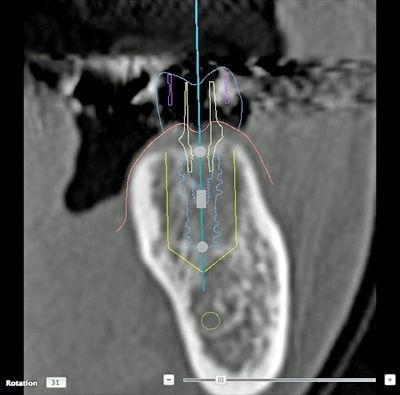

レントゲンでは把握できないことまでCTでは確認することが出来ます。

身体を断面や立体図として見ることができ、骨はもちろんの事、神経や血管に至るまで確認することができます。

そのデータを元に、どのような角度、どのような深さでインプラントを打ち込むかなど、的確な治療計画を立てることができます。